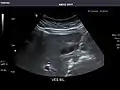

Right kidney